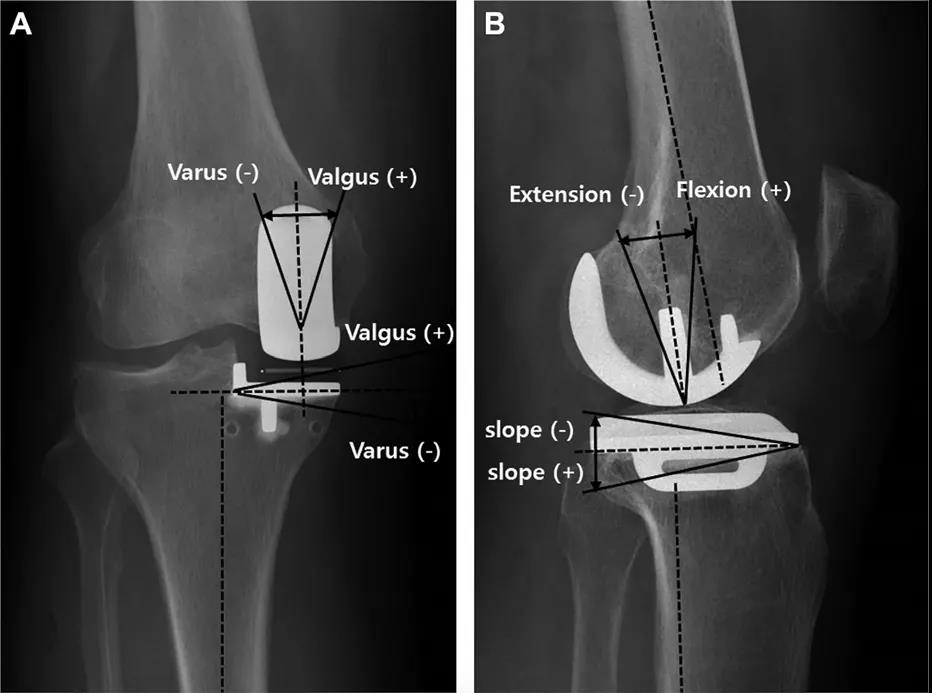

研究者回顾了来自单一中心共253例初次固定平台和活动平台单髁置换手术。所有手术由两名高手术量经正规培训的关节外科医生完成。在他们每年的外科实践中,单髁手术的比例不足10%,平均每人每年行14.2例内侧单髁置换手术。最终我们统计了假体生存率。评价指标包括股骨冠状面成角(FCA),股骨矢状面成角(FSA),胫骨冠状面成角(TCA),胫骨矢状面成角(TSA)和假体悬出。异常值被定义为FCA(偏离中立位±10°以上),FSA(屈曲大于15°),TCA(偏离中立位±5°以上)和TSA(偏离7°后倾±5°以上)。极端异常值被定义为异常值基础上再偏离±2°以上。悬出被定义为前方悬出超过3mm,后方悬出超过2mm,内侧悬出超过2mm。

Methods: We performed a retrospective analysis of 253 primary fixed-bearing and mobile-bearing medial UKAs from a single academic center. All UKAs were performed by 2 high-volume fellowship-trained arthroplasty surgeons. UKAs comprised<10% of their knee arthroplasty practices, with an average of 14.2 medial UKAs per surgeon per year. Implant survival was assessed. Femoral coronal (FCA), femoral sagittal (FSA), tibial coronal (TCA), and tibial sagittal (TSA) angles as well as implant overhang were radio graphically measured. Outliers were defined for FCA (>±10° deviation from neutral),FSA (>15° of flexion),TCA (>±5° deviation from neutral), and TSA (>±5° deviation from 7°). “Far outliers” were an additional >±2° of deviation. Outliers for overhang were identified as >3 mm for anterior overhang, >2 mm for posterior overhang, and >2 mm for medial overhang.